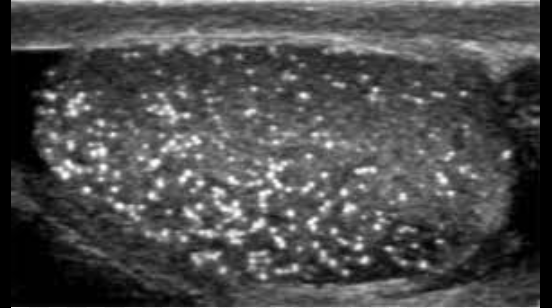

What is this?

Microlithiasis

What risk is associated with microlithiasis?

Increased risk of testicular cancer.